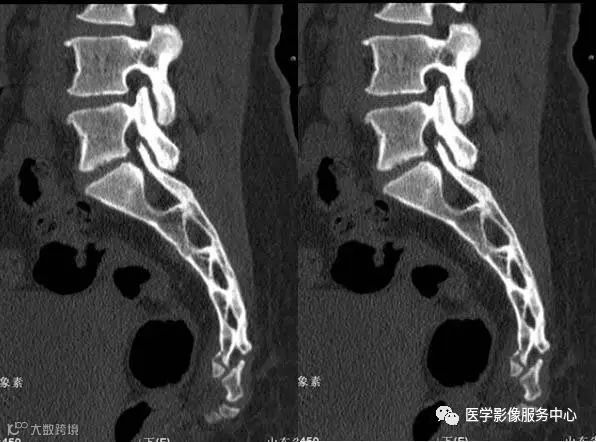

附病例(X线+CT)

病人女性,外伤后骶尾部疼痛,dr片示骶尾关节对应关系差,骶5椎体欠规则。ct重建示骶5椎体粉碎性骨折!

X线

CT